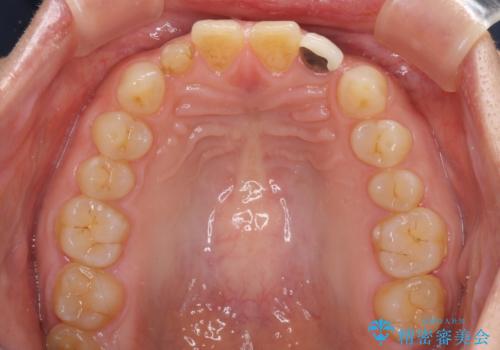

- 前歯の矮小歯に貼り付けられていたラミネートベニアが外れてしまったとのことで来院された患者様です。

反対側の矮小歯は裏打ちが金属であったため、両方の歯ともにオールセラミッククラウンにて補綴することとしました。